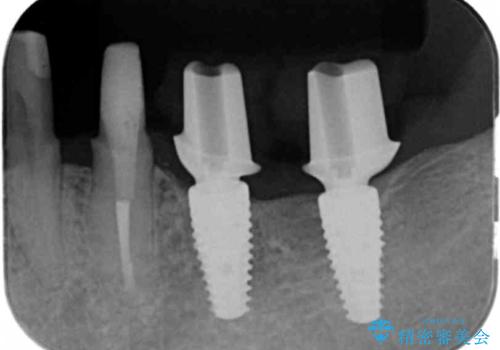

インプラント・ブリッジ補綴を含む、歯周病全顎治療

全体的な歯周病検査を行い、多数の残すことのできない抜歯の必要な歯を認めたため、残せる歯に対しての徹底的な歯周病治療、失った歯に対しブリッジ・インプラント治療を全顎的に行っていくこととしました。